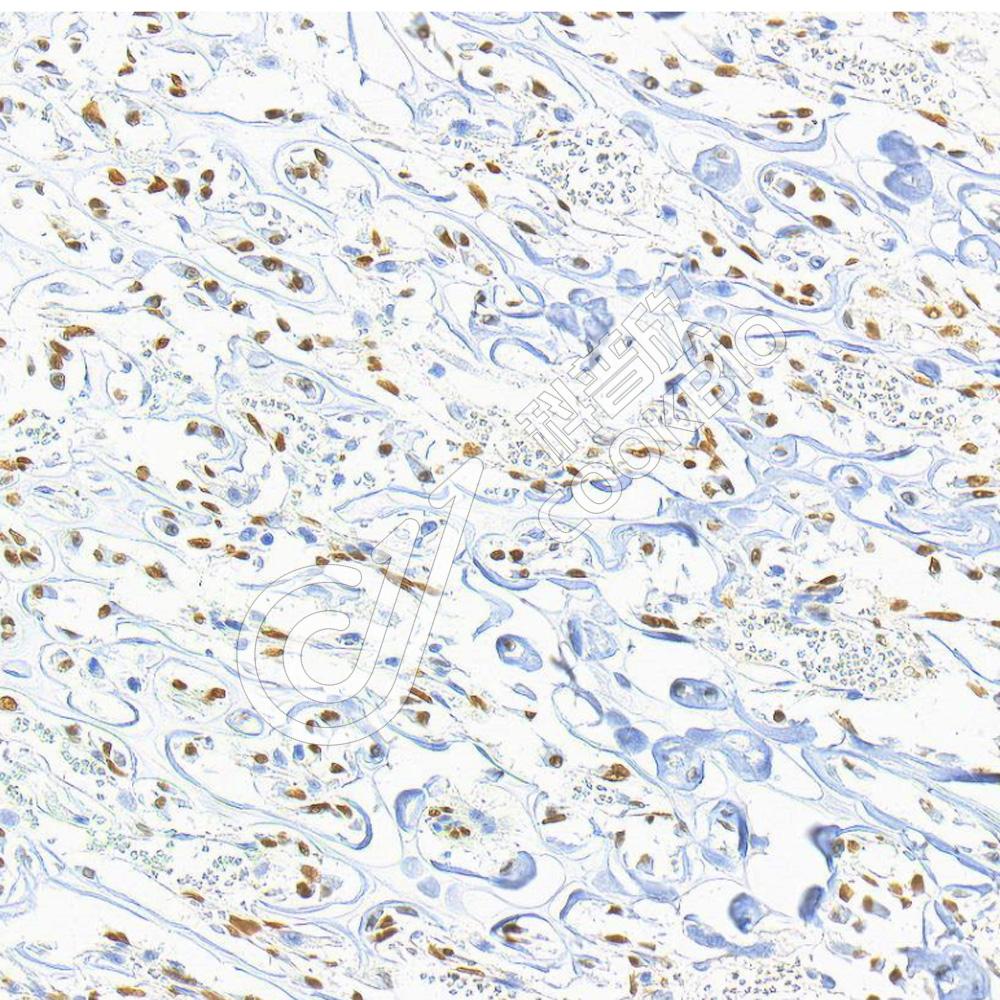

IHC检测RUNX2蛋白(货号 K2376893).

样品: 小鼠骨, 4%多聚甲醛 (货号KSG1101) 固定12-24小时.

抗原修复: 柠檬酸抗原修复液(干粉, pH 6.0) (KSG1201), 高压锅均匀喷气计时2分钟.

—抗: 1: 1000稀释, 4℃ 孵育过夜.

二抗: S-vision免疫组化多聚二抗(山羊抗小鼠), 即用型(货号KB3903), 室温孵育20分钟.